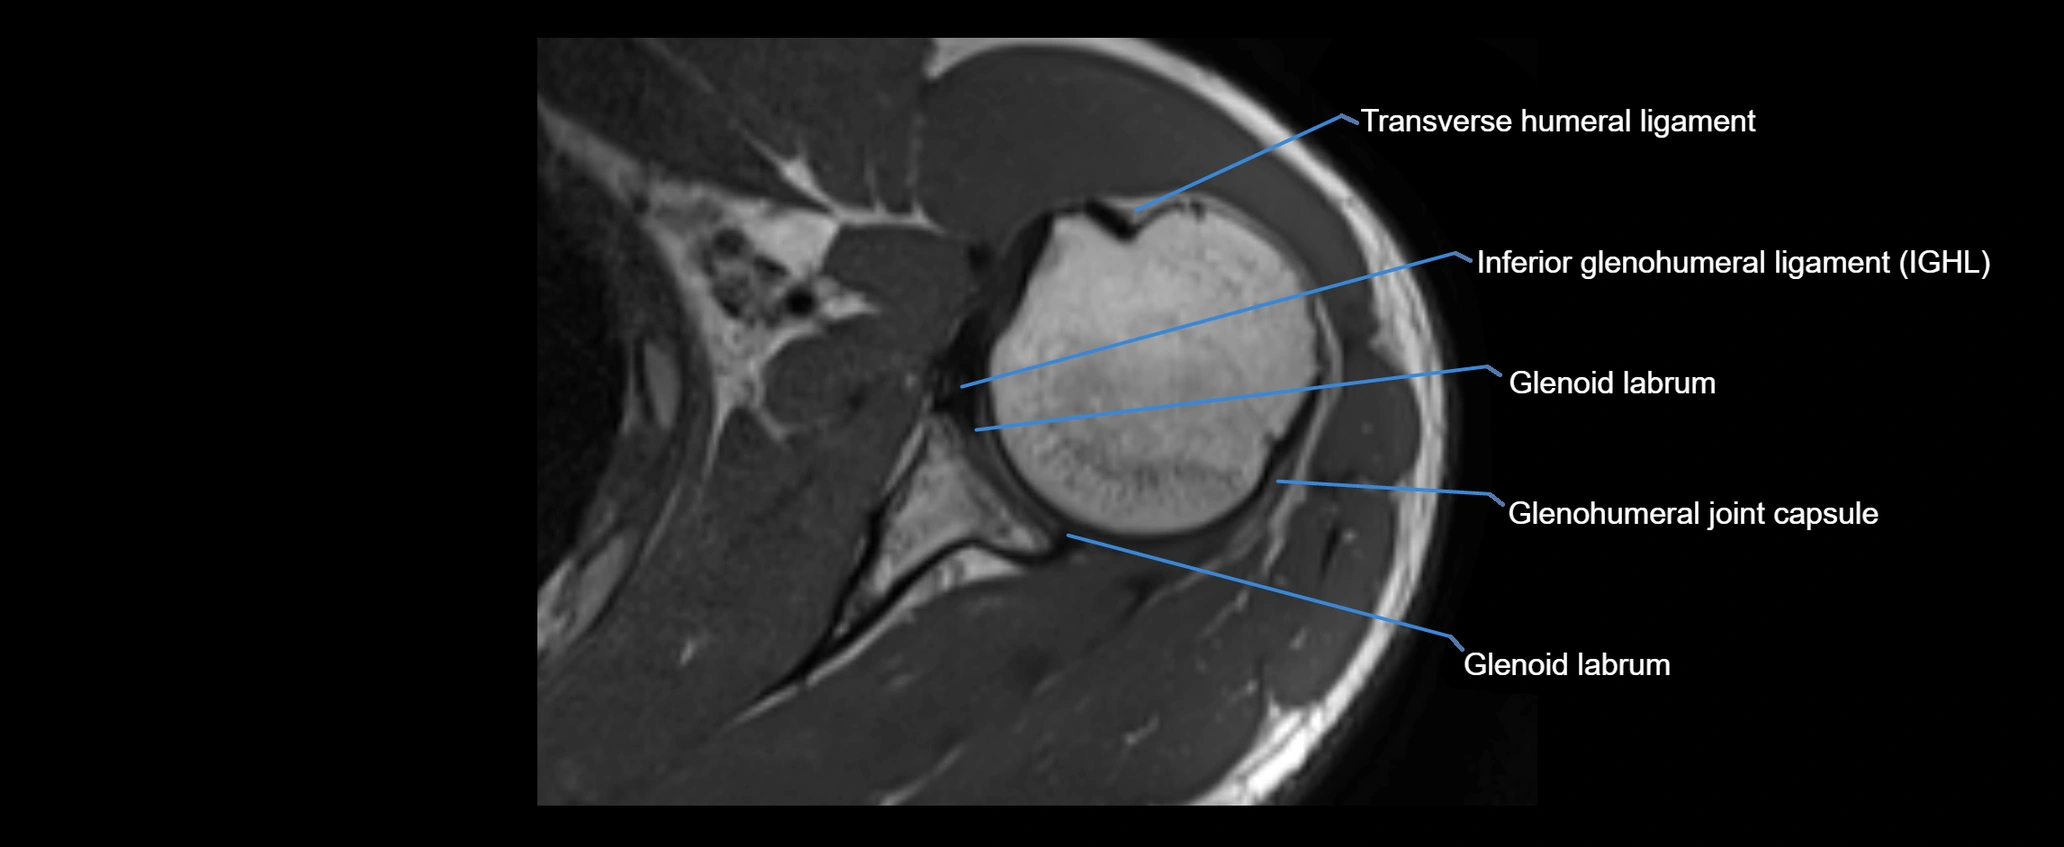

MRI Appearance

• T1-weighted images:

• Normal ligament: Low signal (dark linear band) spanning acromion to clavicle.

• Surrounding fat planes: Bright, delineating the ligament clearly.

• Marrow of clavicle and acromion: Bright due to fatty content.

• Tears: Discontinuity or irregular thickening with intermediate-to-bright signal.

• Chronic injury: Thinning, fraying, or irregular low-signal fibers with adjacent scarring.

• T2-weighted images:

• Normal ligament: Low signal, homogeneous.

• Partial tear or sprain: Focal hyperintensity or thickening.

• Complete tear: Discontinuity with fluid-bright gap between clavicle and acromion.

• Associated edema: Bright signal in distal clavicle or acromion marrow.

• Proton Density Fat-Saturated (PD FS):

• Normal ligament: Low signal, uniform thickness.

• Partial tear or sprain: Bright signal or contour irregularity.

• Complete tear: Clear discontinuity with bright signal gap and joint effusion.

• Excellent for assessing joint capsule, coracoclavicular ligaments, and periarticular edema.

MRI images

image